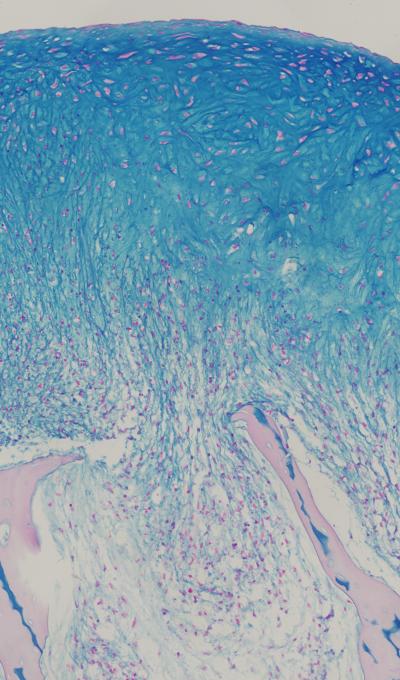

New York, NY—April 30, 2014—Researchers at Columbia Engineering announced today that they have successfully grown fully functional human cartilage in vitro from human stem cells derived from bone marrow tissue. Their study, which demonstrates new ways to better mimic the enormous complexity of tissue development, regeneration, and disease, is published in the April 28 Early Online edition of Proceedings of the National Academy of Sciences ( PNAS ).

"We've been able—for the first time—to generate fully functional human cartilage from mesenchymal stem cells by mimicking in vitro the developmental process of mesenchymal condensation," says Gordana Vunjak-Novakovic, who led the study and is the Mikati Foundation Professor of Biomedical Engineering at Columbia Engineering and professor of medical sciences. "This could have clinical impact, as this cartilage can be used to repair a cartilage defect, or in combination with bone in a composite graft grown in lab for more complex tissue reconstruction."

For more than 20 years, researchers have unofficially called cartilage the "official tissue of tissue engineering," Vunjak-Novakovic observes. Many groups studied cartilage as an apparently simple tissue: one single cell type, no blood vessels or nerves, a tissue built for bearing loads while protecting bone ends in the joints. While there has been great success in engineering pieces of cartilage using young animal cells, no one has, until now, been able to reproduce these results using adult human stem cells from bone marrow or fat, the most practical stem cell source. Vunjak-Novakovic's team succeeded in growing cartilage with physiologic architecture and strength by radically changing the tissue-engineering approach.

Sarindr Bhumiratana, postdoctoral fellow in Vunjak-Novakovic's Laboratory for Stem Cells and Tissue Engineering, came up with a new approach: inducing the mesenchymal stem cells to undergo a condensation stage as they do in the body before starting to make cartilage. He discovered that this simple but major departure from how things were usually being done resulted in a quality of human cartilage not seen before.

Gerard Ateshian, Andrew Walz Professor of Mechanical Engineering, professor of biomedical engineering, and chair of the Department of Mechanical Engineering, and his PhD student, Sevan Oungoulian, helped perform measurements showing that the lubricative property and compressive strength—the two important functional properties—of the tissue-engineered cartilage approached those of native cartilage. The researchers then used their method to regenerate large pieces of anatomically shaped and mechanically strong cartilage over the bone, and to repair defects in cartilage.

"Our whole approach to tissue engineering is biomimetic in nature, which means that our engineering designs are defined by biological principles," Vunjak-Novakovic notes. "This approach has been effective in improving the quality of many engineered tissues—from bone to heart. Still, we were really surprised to see that our cartilage, grown by mimicking some aspects of biological development, was as strong as 'normal' human cartilage."